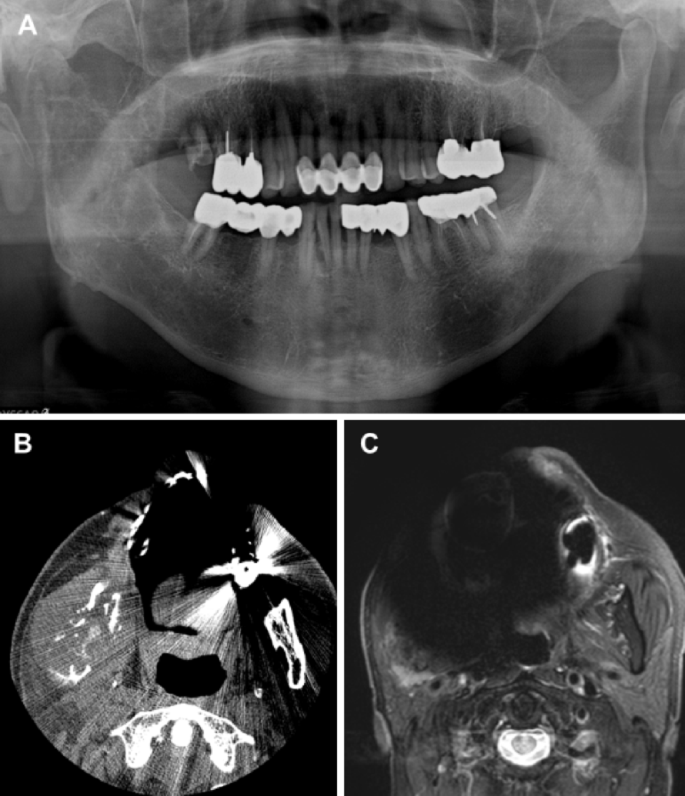

As the population ages, the prevalence of intraoral prostheses—including dental implants—continues to rise. Various prosthetic materials produce metal artifacts due to differences in magnetic susceptibility between the prosthetic material and the surrounding tissues.3,4 Magnetic susceptibility refers to the property of a material to become magnetized when exposed to a magnetic field. While human tissues exhibit weak diamagnetic properties, metals typically have paramagnetic or ferromagnetic characteristics.3,4 When metal is placed within the main magnetic field of MRI, it generates an additional magnetic field in its vicinity, making the main field inhomogeneous and leading to the occurrence of metal artifacts. Metal artifacts are defined as signal intensity distortions and signal loss surrounding a prosthesis and differ in appearance from the metal artifacts observed in computed tomography (CT) or cone-beam computed tomography (CBCT) (Fig. 1).1 These artifacts hinder the accurate assessment of lesion signal intensity and, in severe cases, obscure critical anatomical regions, making diagnosis difficult (Fig. 2). Previous studies have investigated MRI artifacts associated with various types of metallic dental prostheses and materials.5,6 Metal crowns and orthodontic stainless steel wires have been shown to produce more pronounced artifacts, while zirconia and resin materials are associated with less severe artifacts.

A patient with multiple dental prostheses and implants. (A) Panoramic radiograph. (B) Axial CBCT image showing metal artifacts: cupping artifacts (distortion of metallic structure), beam hardening (dark bands), and scatter (white streaks). (C) Axial MR image. Metal artifacts (dashed circle) appear as a dark and bright area adjacent to the prosthesis.